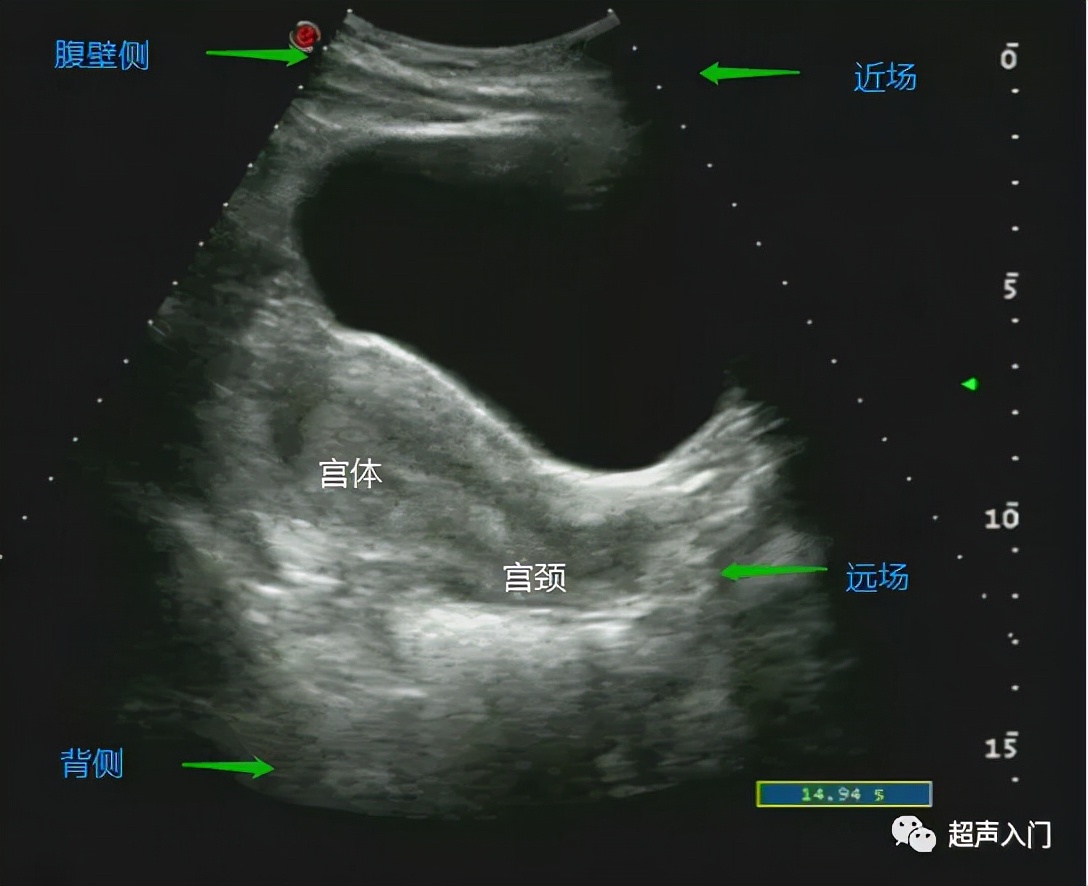

前位子宫(经腹纵切面)

通过上图我们可以看出,宫体靠近腹壁侧(人体前方),因此上图为前位。